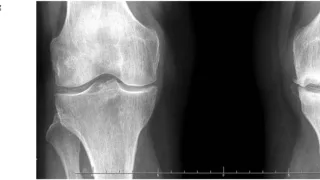

午前の病院での仕事今朝も小雨.気温は, 6 ℃.8時前に病棟に上がって, 昨日後輩医師の執刀で関節鏡下外側半月板縫合術が行われた高校生の患者さんの経過を確認.問題なく, 今日からリハビリを開始できそうです.8時から朝の病棟回診.9時前に外来...